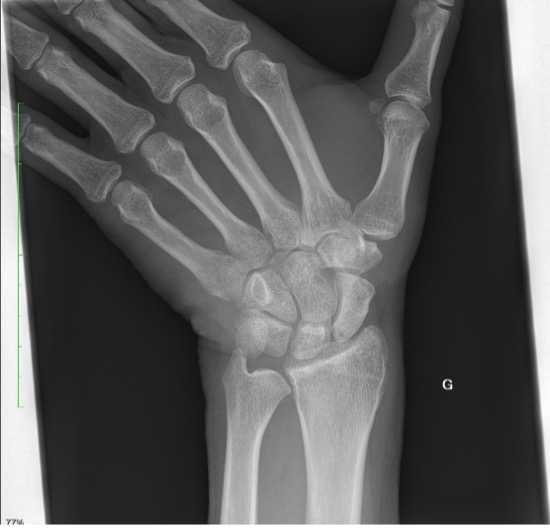

Un patient se présente pour des douleurs au niveau du poignet gauche, suite à une chute à vélo avec réception sur la paume de la main. Cliniquement, nous observons un œdème au niveau du dos de la main, des douleurs à la mobilisation du poignet avec une discrète limitation de l’extension et une prono-supination conservée.

La radiographie effectuée révèle une fracture du triquétrum. Les fractures du triquétrum (ou os pyramidal) sont les fractures du poignet les plus fréquentes après celles du scaphoïde, représentant 13% des fractures des os du carpe. Elles résultent habituellement d’une chute sur la main en hyperextension et déviation ulnaire. Elle est fréquemment retrouvée chez des pratiquant·es de sports de combat.

Il existe trois types de fractures du triquetrum : les fractures corticales dorsales, les fractures du corps et les fractures corticales palmaires. Pour ce patient, il s’agit d’une fracture de type 1 (95% des cas), qui est une fracture par avulsion associée à des lésions des ligaments dorsaux du carpe et considérée comme une « entorse grave du poignet ».

Les fractures corticales dorsales sont les plus courantes et sont généralement bénignes, tandis que les fractures corticales palmaires sont les moins courantes et peuvent poser des problèmes.

La clinique est aspécifique mais le diagnostic doit être évoqué face à des douleurs sur le côté ulnaire du carpe, après une chute main en extension. Les fractures du triquetrum passent facilement inaperçues sur les radiographies conventionnelles du poignet, mais elles sont souvent associées à des lésions ligamentaires importantes conduisant à une instabilité du carpe, ou évoluent vers une pseudarthrose. Un complément par CT (ou IRM) peut être nécessaire afin de confirmer le diagnostic et préciser les lésions.

La prise en charge est la plupart du temps conservatrice avec une immobilisation rigide par attelle AB pendant 3-6 semaines, avec généralement de bons résultats. Le traitement chirurgical est indiqué pour les fractures présentant un déplacement important ou des signes d'instabilité. Les complications des fractures du triquetrum comprennent les lésions du complexe fibrocartilagineux triangulaire (TFCC) et l'arthrite pisotriquetrale.